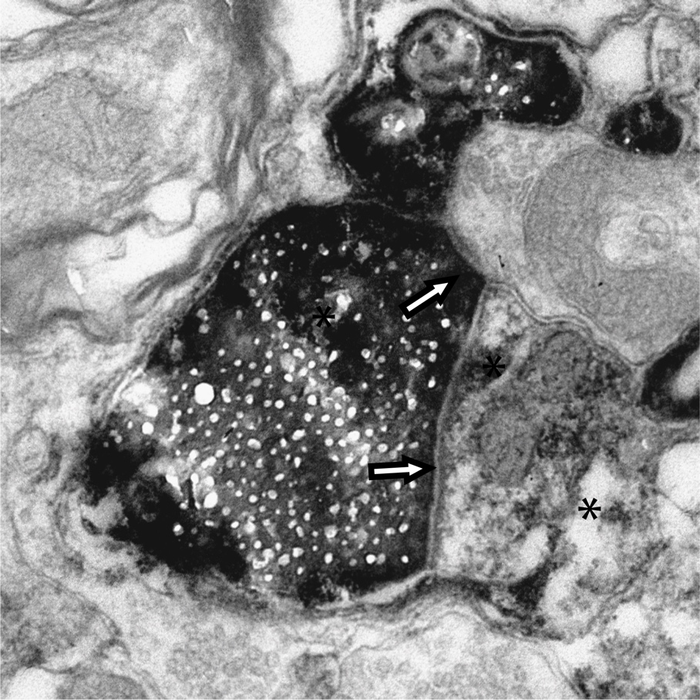

image: Scripps Research scientists tracked proteins tagged with biotin (black areas of this electron microscopy image) from retinal cells (pictured) to the visual cortex of the brain. view more

In the new work, Cline and her colleagues used a method of labeling proteins that ensured they only tracked proteins that stay intact. The tag, a biotin molecule, cannot be reintegrated into new proteins if the proteins are disassembled. The research team introduced the tag into retinal ganglion cells in the eyes of rats. Eleven days later, they examined cells from the visual cortex, an area of the brain responsible for processing vision and physically distant from the retinal ganglion cells.

The researchers also used a different set of protein tags to show that, in most cases, these proteins were being transported between cells inside exosomes—small, membrane-enclosed compartments packed with proteins, like suitcases packed with clothes. This discovery can help pave the way for other researchers who want to follow protein movements in other areas of the brain, as well as compare interneuronal protein transport in healthy versus diseased brains. While the new work was carried out in the visual system, Cline says there’s no reason not to think the results are further reaching.